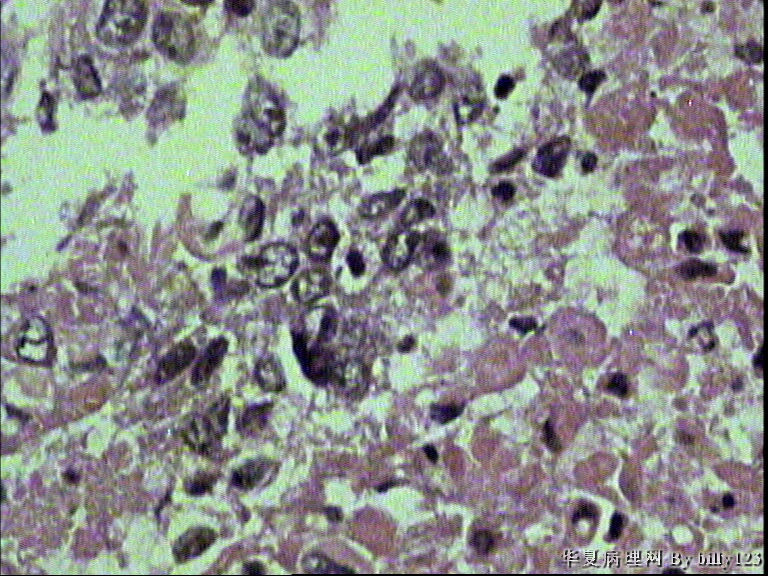

支气管活检,患者,男性,66岁,支气管镜下见息肉样新生物,鳞癌吗?请各位老师指教!

• 支气管活检,患者,男性,66岁,支气管镜下见息肉样新生物,鳞癌吗?请各位老师指教!图2

图2

棘层松解型鳞癌

从第二,三张图片的组织结构是鳞癌

鳞状上皮重度不典型增生,局部可疑浸润。

如果全面观察过切片确实没有浸润,可诊断为原位鳞癌。

全层有不典型增生 有坏死 考虑鳞癌